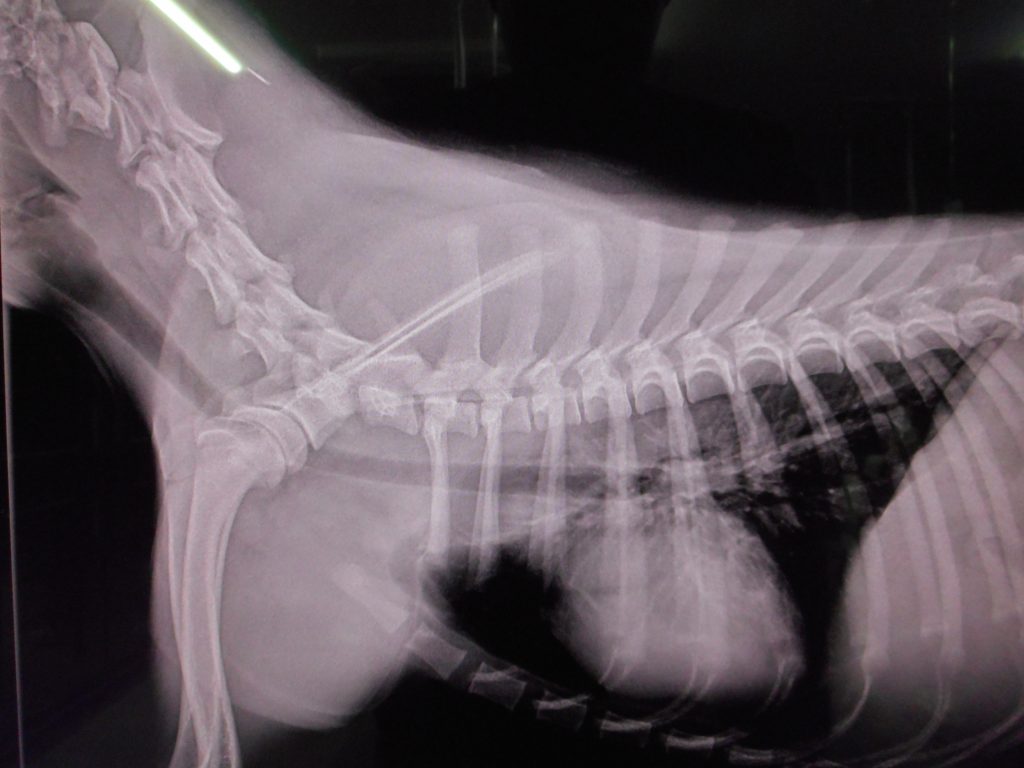

全身のレントゲン検査開始

胸部の写真で肺はOKだが・・・

診断:第2頸椎骨折

これで全身麻痺の原因が判明です

頸と動かさないように丁寧な処置が必要となりました

其の後全身のレントゲン検査では異常なく、血液検査で全身打撲が判明しました

Traffic accident emergency

have been diagnosed with a cervical spine fracture by X-ray

It’s life-threatening